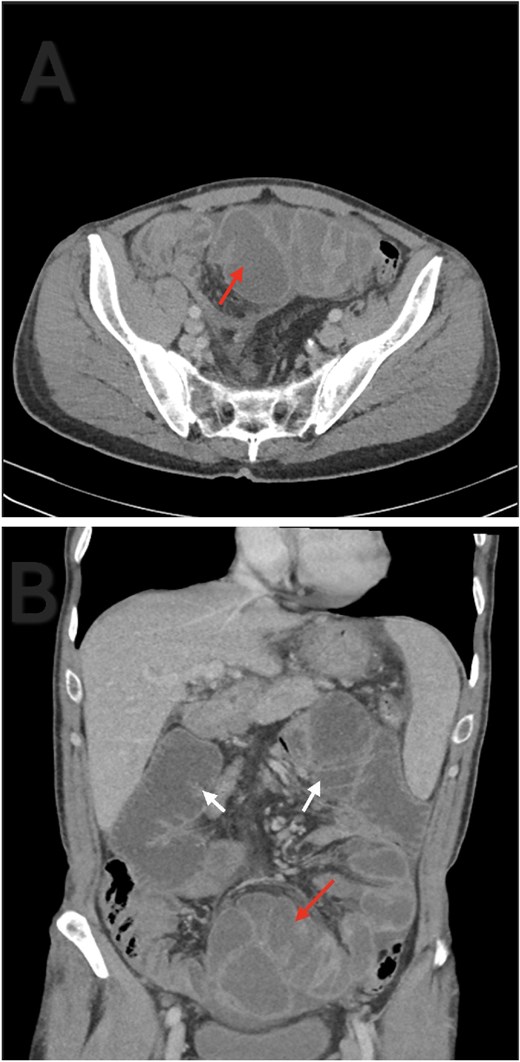

A 56-year-old male patient presented to the emergency department with generalized abdominal pain, obstipation, and vomiting for six days. On examination, there was diffuse generalized abdominal tenderness and a palpable mass in the hypogastric region. Contrast enhanced abdominal computed tomography (CT) revealed clustered ileal loops in the pelvis with multiple transitional zones and dilated proximal small bowel loops (Fig. 1).

Axial (A) and coronal (B) contrast enhanced abdominal CT. Ileal loops congregated at the pelvis (red arrow). Small bowel loops dilation (white arrow).

CT is the imaging modality of choice, with typical findings including clustered or ‘cauliflower-like’ bowel loops and peritoneal thickening. In our patient, CT revealed clustered ileal loops and transitional zones, raising suspicion for mechanical obstruction. Histopathology, though seldom needed, can support SEP diagnosis by revealing fibroconnective tissue growth, inflammation, and dilated lymphatics. Absence of granulomas, giant cells, or birefringent material helps to rule out tuberculosis [9].